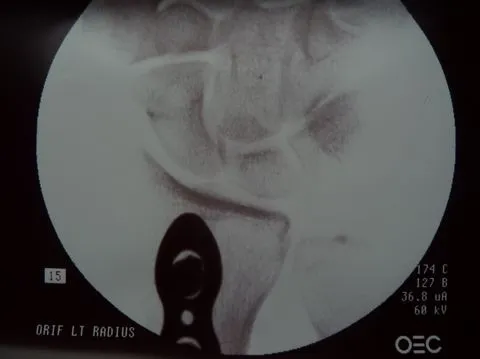

Dr. Gray used flouroscopy to confirm that the fracture margins were in perfect alignment, secured by three screws proximal and three screws distal to the fracture.

In fact, one view (below right) shows such tight apposition and such perfect alignment, that one cannot even see the fracture margins.

Dr. Gray checked all of her wrist bones (left), applied a new plaster splint and a new sling, and Alison's I.V. line was removed about 2.5 hours after it was inserted. What a great surgeon and professional team!